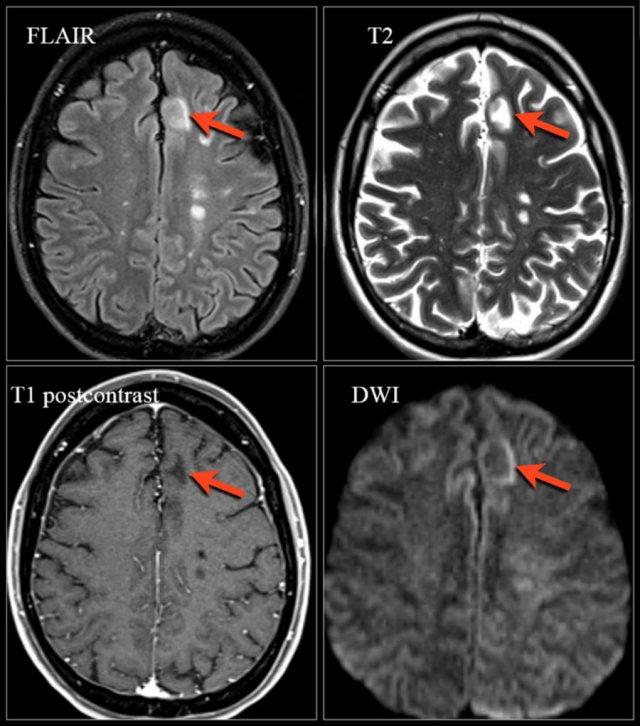

Ở ngoài cùng bên trái là tổn thương mới tăng tín hiệu T2 trên phim chụp theo dõi 3 tháng sau sự kiện lâm sàng đầu tiên.

Các hình ảnh bên phải cho thấy tổn thương ngấm thuốc mới trên phim chụp theo dõi.

Chuỗi xung T1W: Các tổn thương ngấm thuốc trên phim chụp ban đầu và các tổn thương ngấm thuốc mới trên phim chụp theo dõi 3 tháng sau.

Ngấm thuốc tương phản từ

Ngấm thuốc là một đặc điểm điển hình khác của MS.

Đây là hình ảnh của một bệnh nhân được tái khám 3 tháng sau đợt tấn công lâm sàng đầu tiên.

Các đặc điểm điển hình của MS được thấy trong trường hợp này bao gồm:

- Nhiều tổn thương ngấm thuốc.

- Nhiều tổn thương trong số này “tiếp xúc với vỏ não” và phải nằm ở vị trí các sợi chữ U.

- Tất cả các tổn thương ngấm thuốc này đều là tổn thương mới, vì sự ngấm thuốc Gadolinium chỉ tồn tại trong khoảng 1 tháng.

- Do đó, phát hiện này là bằng chứng của sự phát tán theo thời gian (dissemination in time).

Phù nề xung quanh tổn thương mới sẽ thoái lui dần và cuối cùng chỉ còn lại phần trung tâm tồn tại như một tổn thương tăng tín hiệu trên chuỗi xung T2W.